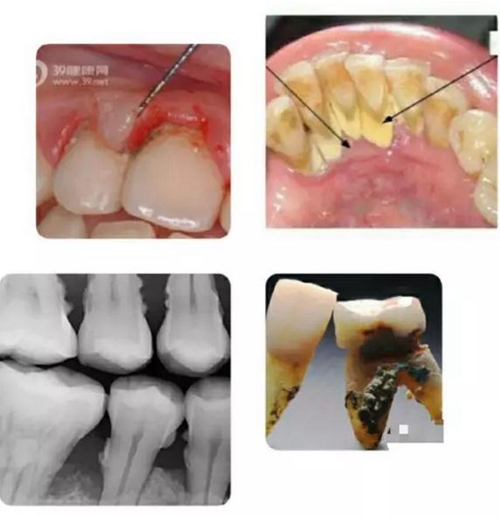

如上圖所示,無論是肉眼直視,還是在X光片上顯現(xiàn),以及拔下的牙齒之上,牙周病患者的牙根面上都可見附著著大大小小的牙結(jié)石。

寄居在牙結(jié)石里的細(xì)菌可以釋放大量毒素,導(dǎo)致牙齦發(fā)炎,溶解,與牙面分離,從而突破牙槽骨保護的第一道屏障;繼而進一步直接使牙槽骨發(fā)炎,溶解,萎縮。若無牙科治療介入,牙槽骨可以被溶解殆盡,最終牙齒自行脫落。一般來講,牙齒上的牙結(jié)石越大越多,寄居的細(xì)菌就越多,牙周病就發(fā)展得越迅速越嚴(yán)重。

上列組圖大致列出了牙結(jié)石的成因: 首先是牙齒的復(fù)雜形狀與排列,形成有很多死角空間 ;其次是我們吃的食物會進入到這些死角空間里,而目前人們的刷牙工具和方法與各人刷牙的效果并不能保證所有食物殘渣被完全清除干凈。于是混合著口腔中天然存在的細(xì)菌,在舌肌頰肌唇肌等口腔周圍肌肉的擠壓下,殘留食物便緊粘在牙面上,并沉積了唾液中所含的鈣質(zhì)后,便形成了堅硬的牙結(jié)石,靠自己刷牙不可去掉。必須由經(jīng)過專業(yè)訓(xùn)練的牙醫(yī)或潔牙員使用專門工具才能清除。